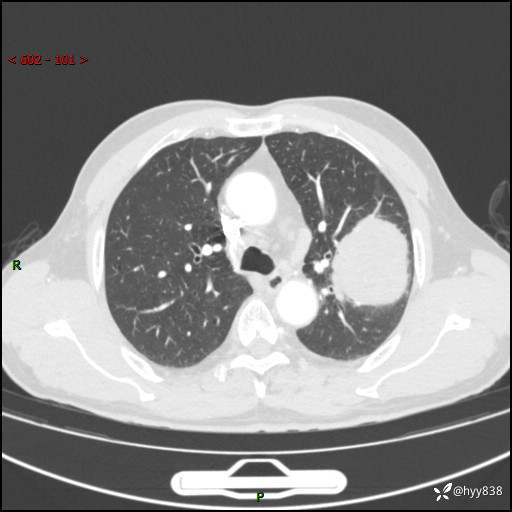

68岁/男,发现左下肺占位5天。如此大的肿块,患者竟然没有症状---结果公布~

【患者信息】:68岁/男

【主诉】:检查发现左下肺占位5天。

【现病史及既往史】:患者于4天前外院行“经尿道钬激光碎石术”,住院期间胸部CT检查发现左下肺肿块,患者平素无明显咳嗽咳痰,无心慌、胸闷、胸痛、呼吸困难、低热、盗汗,无头痛、头晕,无腹痛、腹胀等不适,现患者为求进一步治疗,遂来我院就诊,以“左下肺肿块”收入我科。 患者自起病以来,精神可,睡眠可,饮食可,大小便正常,体重无明显改变。

【检查】:胸部CT增强扫描